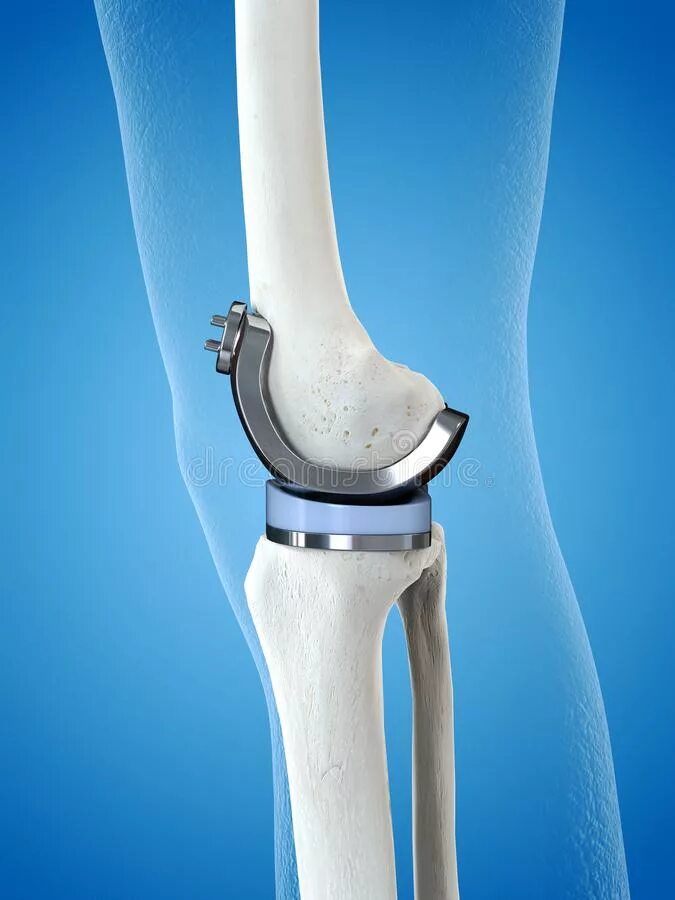

Протезы суставов отзывы